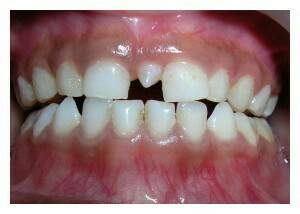

Es paciente femenina de 6 años de edad con hallazgo clínico y radiográfico de mesiodents. Además presencia de diastema interincisal lo que ha ocasionado timidez en la interrelacion de la portadora al sonreir (sonrisa labial, sin mostrar dientes) al interrogatorio la representante refiere burlas en la escuela por su condición.

Despues del examen realizado se procedio a planificar intervención quirurgica simple para la extración del mesiodent. Acto operatorio sin complicación postoperatorio mediato a los 3 dias satisfactorio; se observa aumento de autoestima y confianza al sonreir.